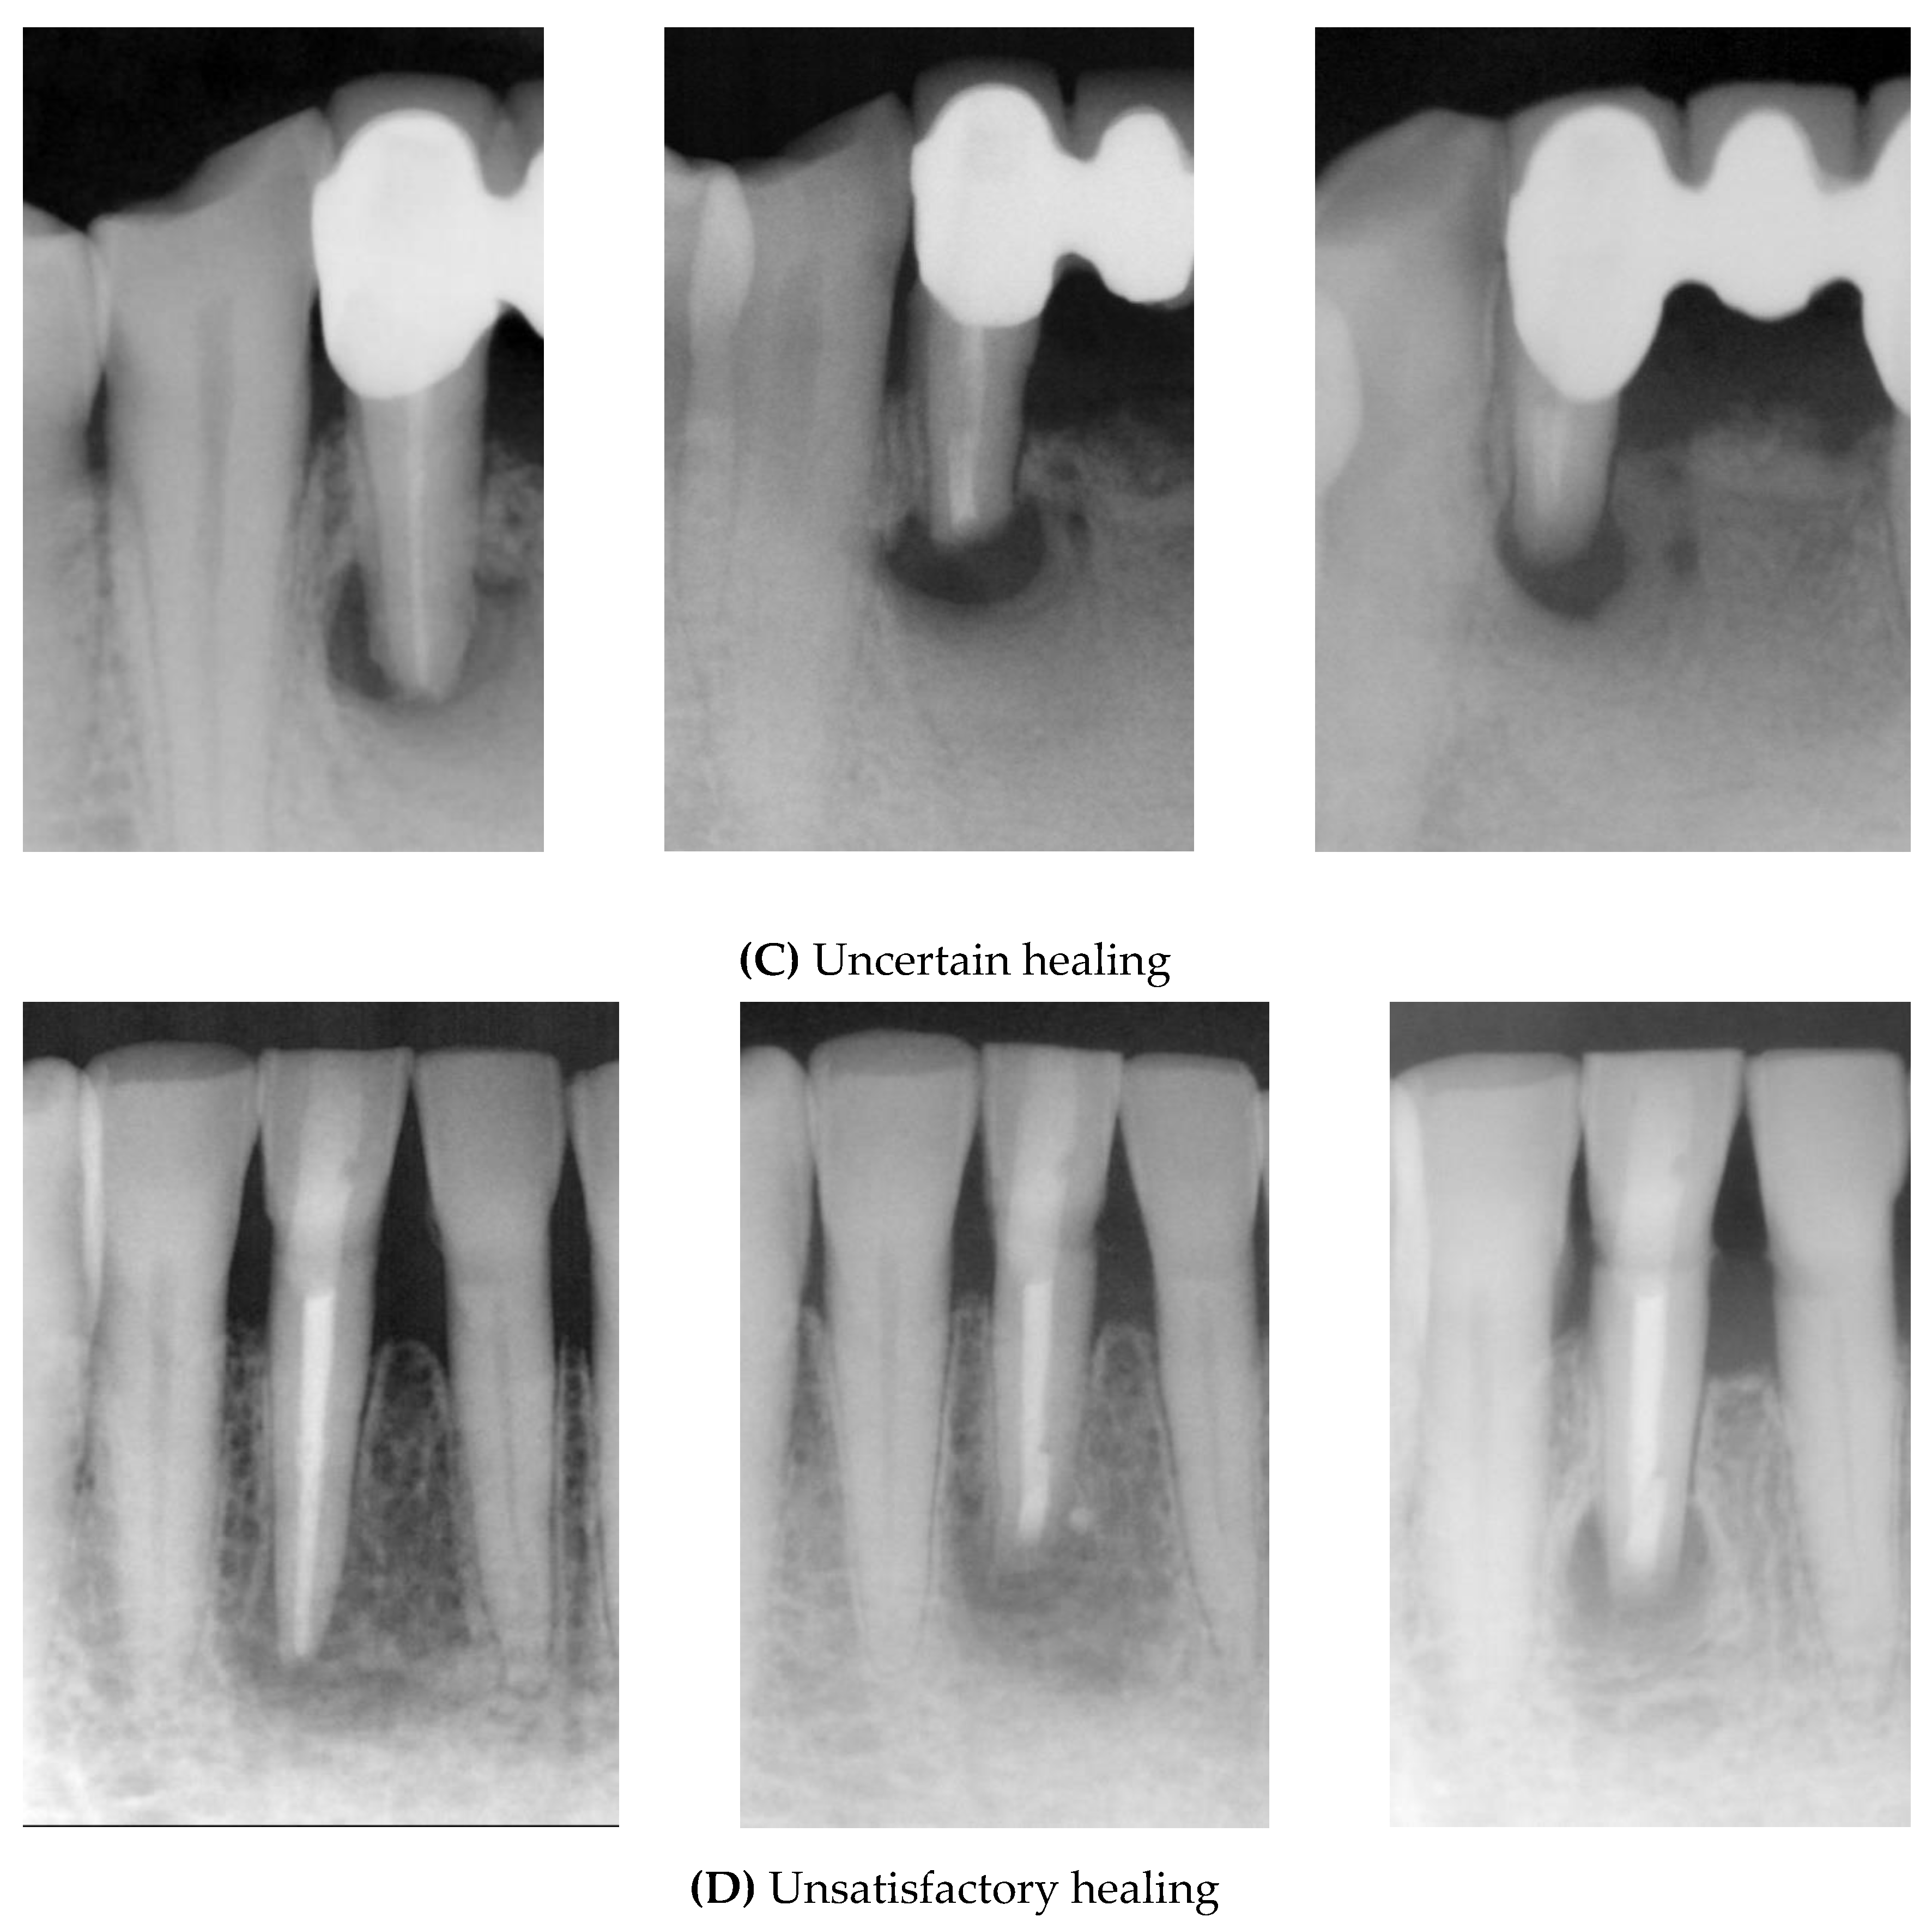

- Complete healing: the periodontal space has reformed around the apex, which is less than twice the width of the noninvolved parts of the root; complete bone repair with no apical periodontal space.

- Incomplete healing: the rarefaction has decreased or remained and is characterized by one or more of the following findings: irregular periphery of the rarefaction, the rarefaction is located asymmetrically around the apex, the connection of the rarefaction with the periodontal space is angular, and isolated scar tissue in the bone is observed with these findings.

- Uncertain healing: rarefaction has decreased in size, and is accompanied by one or more of the following findings: the rarefaction is larger than twice the width of the periodontal space; it has a circular or semicircular periphery; it is located symmetrically around the apex as a funnel-shaped extension of the periodontal space; and bony structures are discernible within the bony cavity.

- Unsatisfactory healing: the rarefaction has enlarged or has remained unchanged.